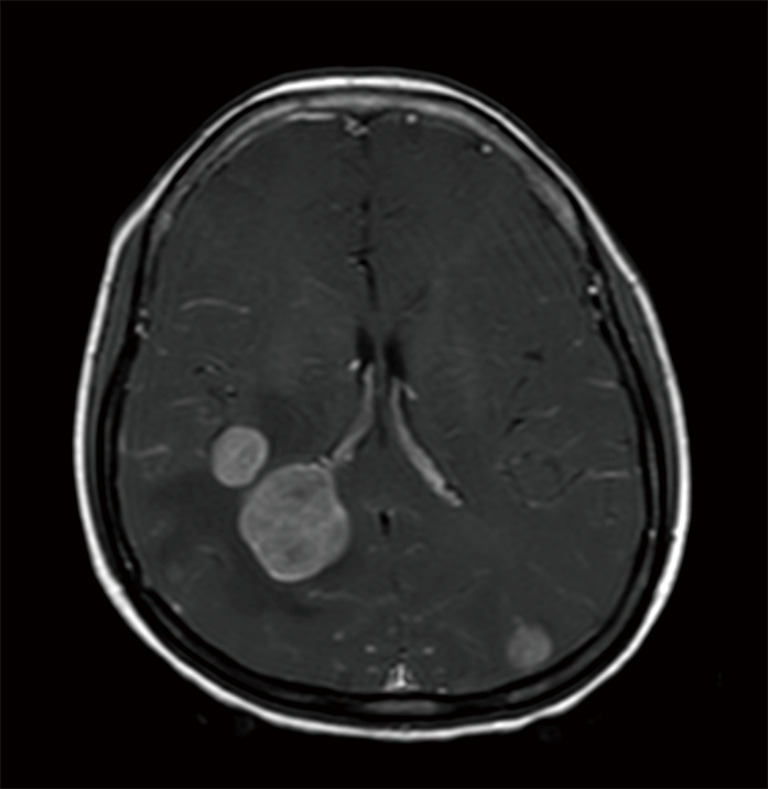

Radiotherapy Of Brain Metastasis From Lung Cancer In Limited Resource